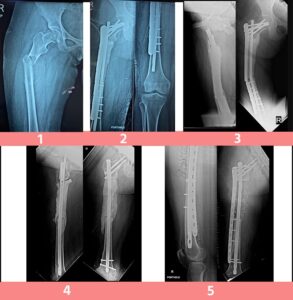

Fracture shaft of humerus

A young gentleman came with fractured arm following an injury in the emergency. He was given temporary splintage and first aid at that time to decrease the pain. Next day he was operated with fracture fixation and mobilized immediately after the operation. Next day he became comfortable and discharged happily ... Read more..